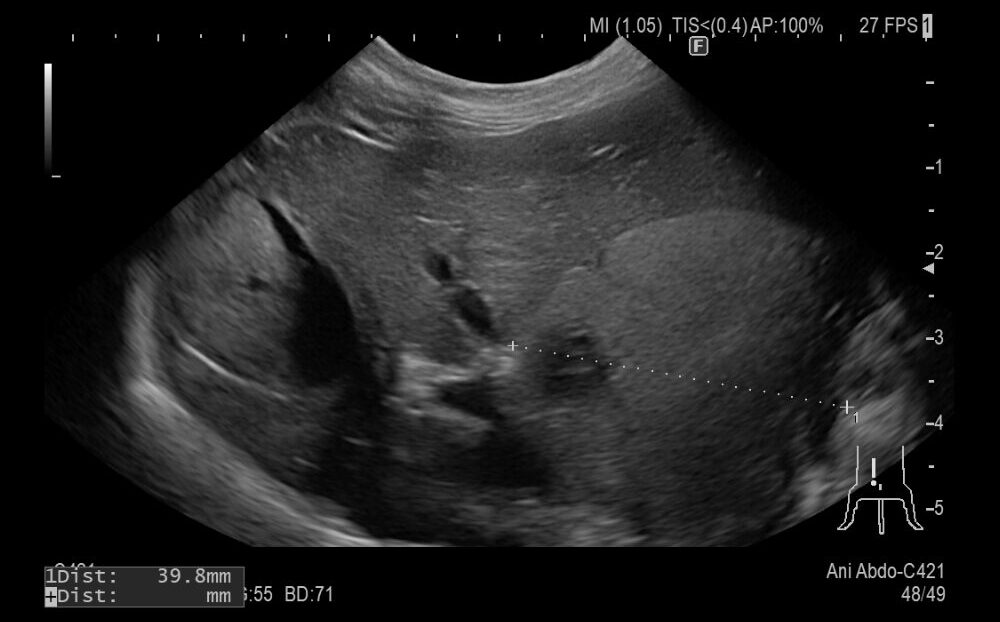

症例は9歳の柴犬でかかりつけにて肝臓に腫瘍が見つかったが、手術が難しいとのことで来院されました。

超音波で確認すると肝臓の基部に腫瘍が認められました。犬の肝臓腫瘍は肝細胞癌の可能性が高いので、摘出を行いました。